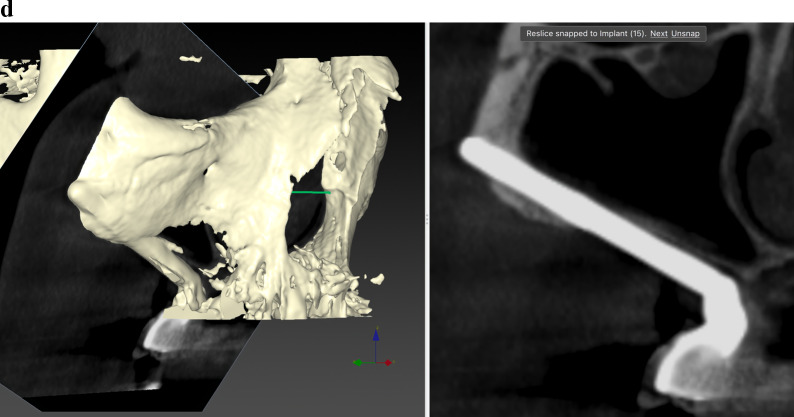

Results: Twenty patients were treated. Ten patients received two ZIs and regular implants; one received three ZIs plus regular implants, and nine received four ZIs. Fifty-nine ZIs were placed: thirty-six (61%) Straumann ZAGA-Flat implants and twenty-three (39%) Straumann ZAGA-Round implants. Four patients (20%) presented earlier sinus floor discontinuities. Fifteen patients (75%) had prior sinus opacities. Nineteen patients were followed for between 38 and 53 months (mean 46.5 months). One patient dropped out after 20 months. When comparing pre-surgical CBCT with post-surgical CBCT, 84.7% of the sites presented identical or less sinus opacity; nine locations (15%) showed decreased, and another nine increased (15%) post-surgical sinus opacity. Fifty-three ZIs (89.8%) maintained stable soft tissue. Six ZIs had recessions with no signs of infection. ZIs and prosthesis survival rate was 100%.